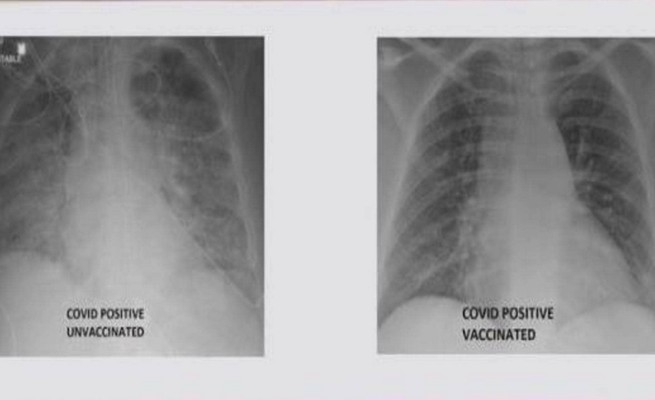

صور الأشعة تكشف أثر كورونا على رئة شخص ملقح و آخر غير ملقح

نشر الطبيب العربي في الولايات المتحدة، غسان كمال، صورة تظهر الفرق بين رئتي شخص جرى تطعيمه ضد فيروس كورونا ورئتي شخص آخر لم يتلق التطعيم، مشيرا إلى أن الاثنين أصيبا بفيروس كورونا.

وأظهرت صور الأشعة السينية أن رئتي الشخص غير الملقح، المصاب بفيروس كورونا كانت بيضاء بصورة شبه كاملة وتعرف بـ”عتامة الرئة”، مما يعني أنها كانت غارقة في الفيروس، في حين أبرز صور رئتي الشخص ببيضاء أقل.

وتعني صورة الأول أيضا نقصا في دخول الهواء إلى رئتيه، فيما تعني لدى الثاني أن الهواء يتدفق بسهولة علاوة على أن رئتيه خاليتين من الوباء.

وأشار إلى أنه نشر الصور من أجل إظهار الفرق الذي يمكن أن يحدثه اللقاح في رئتي الشخص في حال إصابته بالفيروس.